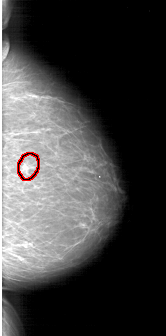

RIGHT_CC LINES 6046 PIXELS_PER_LINE 2986 BITS_PER_PIXEL 12 RESOLUTION 43.5 OVERLAY

FILE: A_1403_1.RIGHT_MLO.OVERLAY

TOTAL_ABNORMALITIES 1

ABNORMALITY 1

LESION_TYPE MASS SHAPE IRREGULAR MARGINS SPICULATED

ASSESSMENT 5

SUBTLETY 5

PATHOLOGY MALIGNANT

TOTAL_OUTLINES 1

BOUNDARY